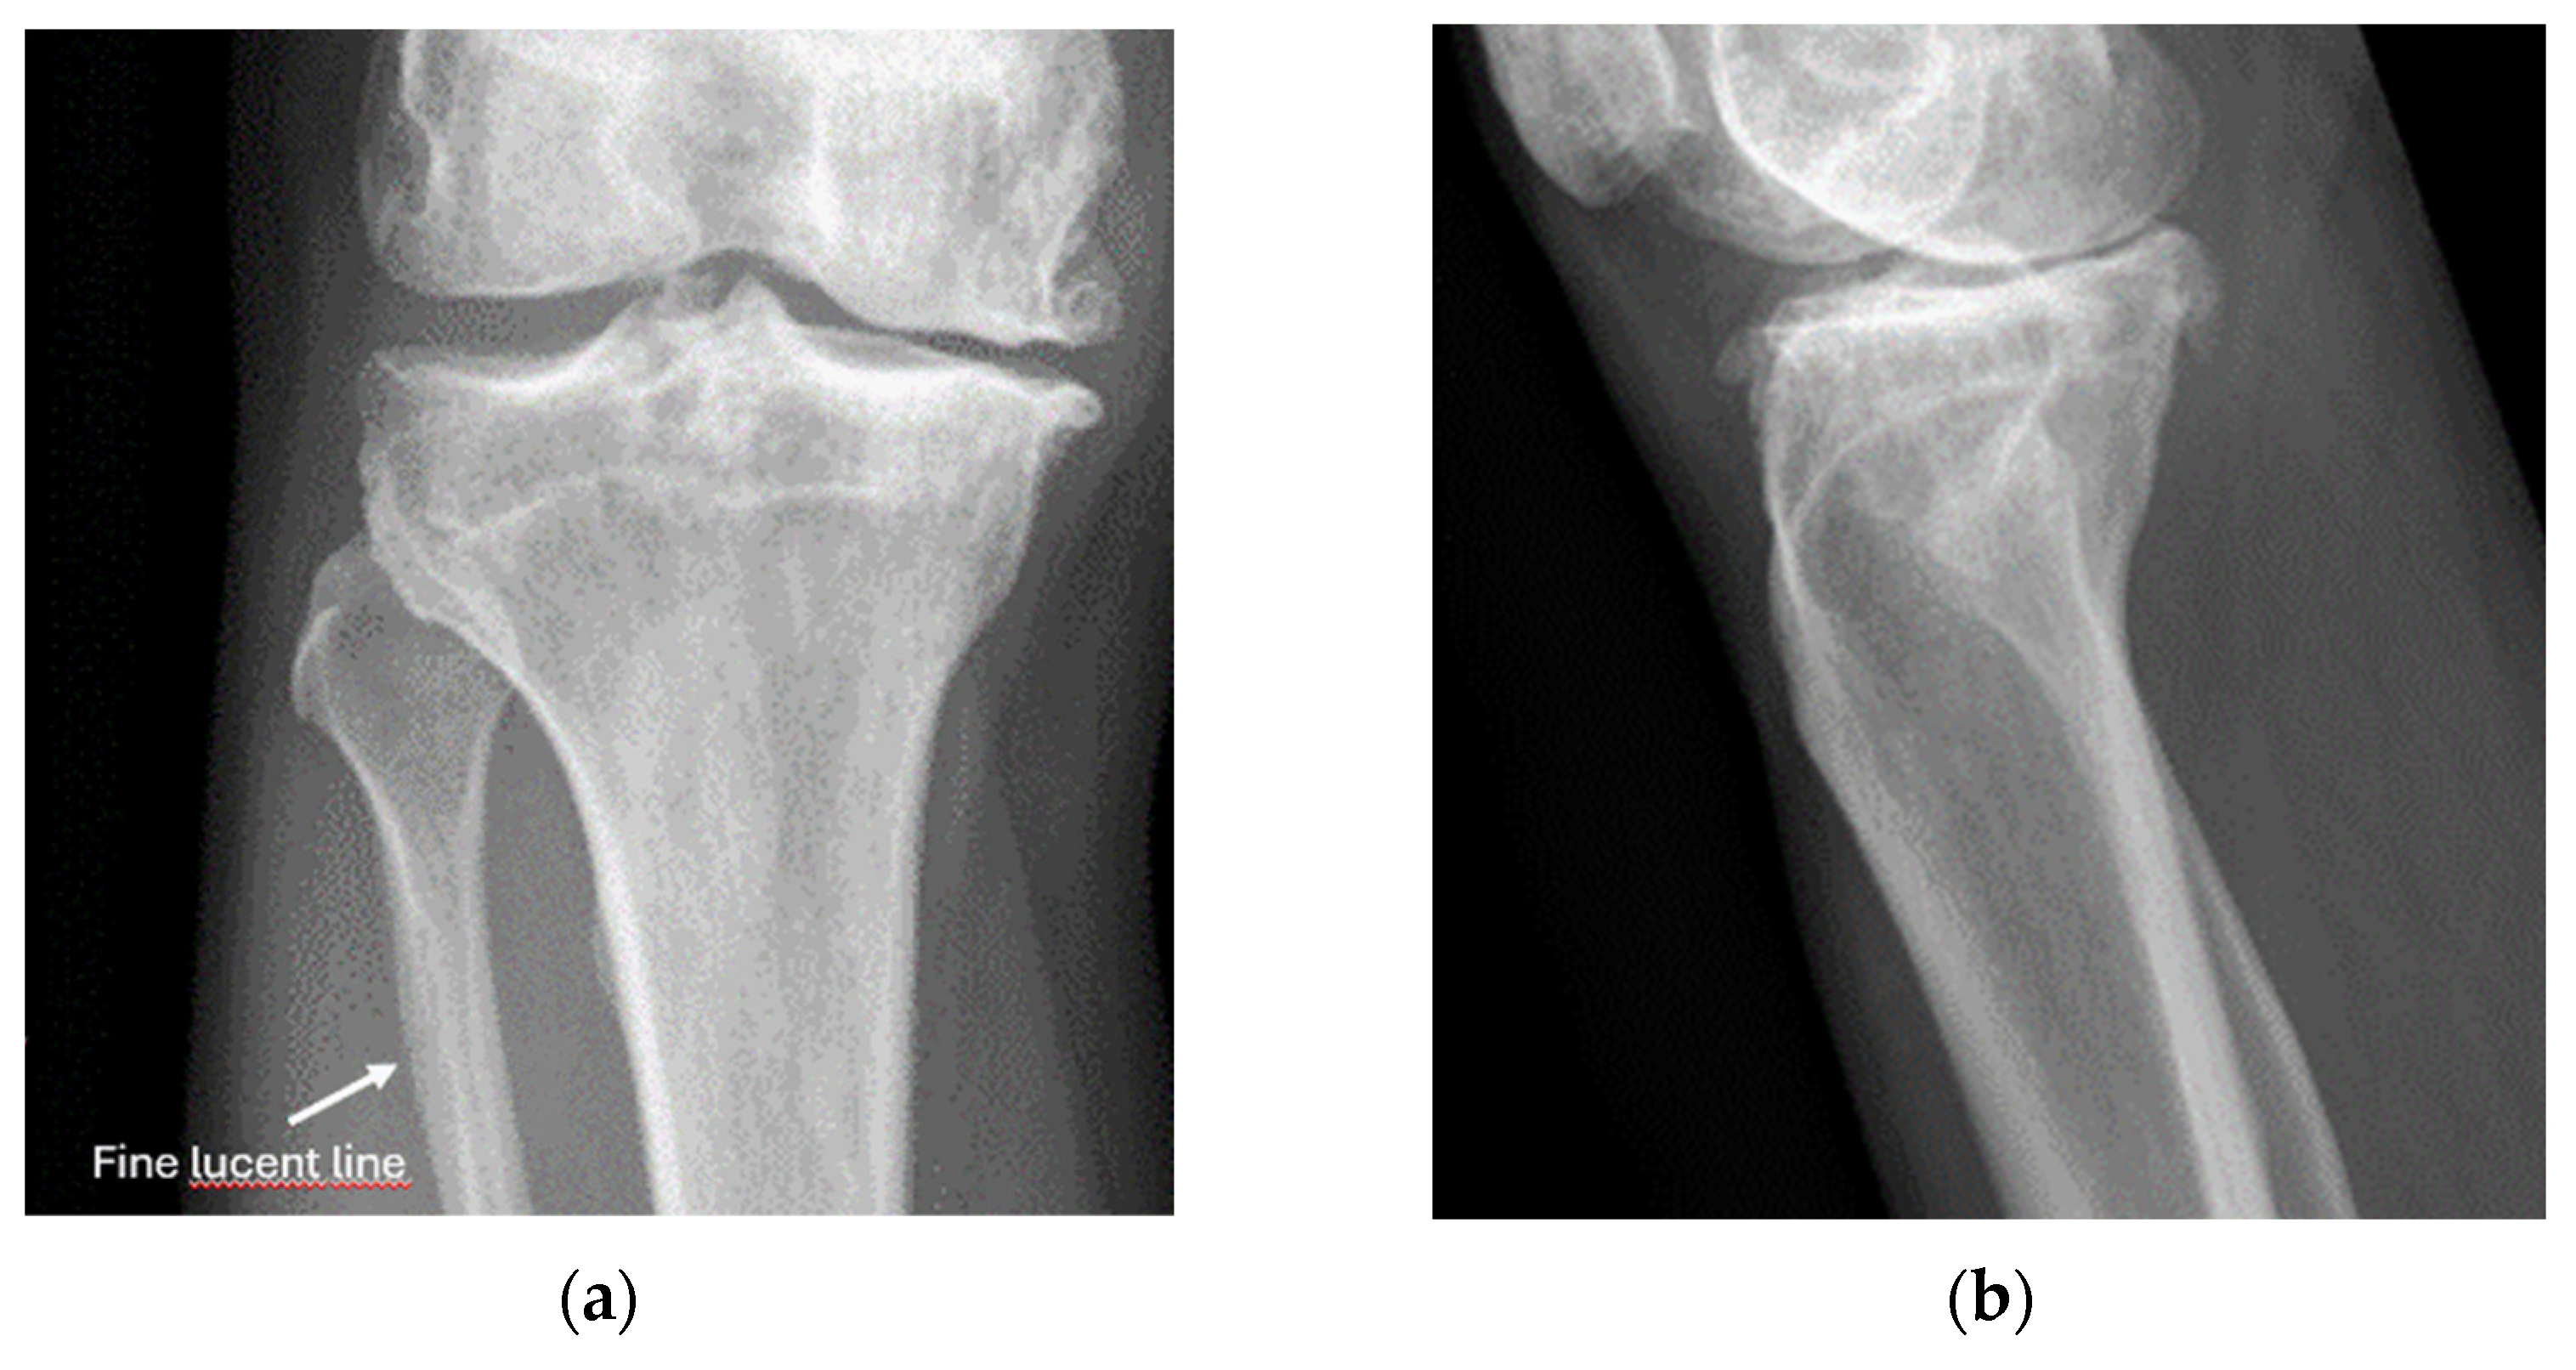

- Example: Stress Fracture

8.2. Screening of Patients with Suspicion of Occult and Stress Fractures (Figure 11 and Figure 12)

- Recommendation 2: Given the promising but limited evidence, ultrasound should be considered a first-line imaging tool for suspected occult fractures, except in the pelvis and vertebral column.

- Recommendation 3: Ultrasound should be used as first-line imaging for suspected stress fractures, with follow-up X-ray if evidence of a stress fracture is identified. Exceptions include pelvic and vertebral column fractures.